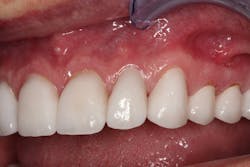

Chris returned for us to cement the crowns. The lab had fabricated exquisite-looking crowns that function properly (figures 7–9). We prepped the uppers in one day, lowers in another day, and cemented all in one day.

Figure 7: Final crowns

Figure 8: Final crowns

Figure 9: Final crowns